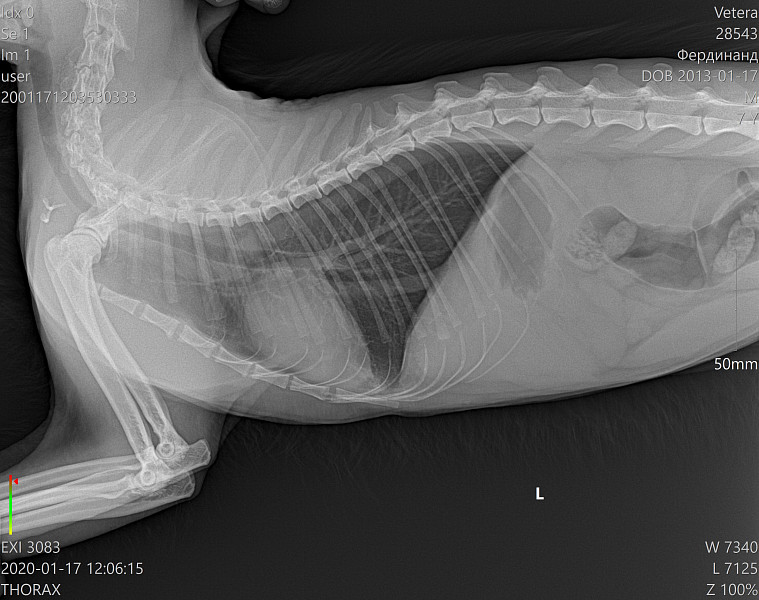

Истончение костей у кошек: причины и решения